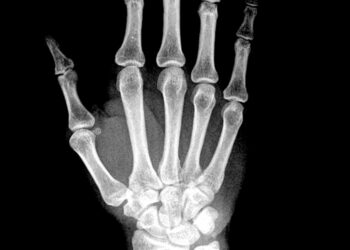

Skaityti daugiauDetailsMeloreostozė – itin retas kaulų susirgimas, paveikiantis kaulų išorinius sluoksnius ir paskatinantis naujo kaulinio audinio formavimąsi. Ši liga dažniausiai pasireiškia...